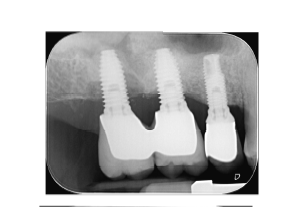

Péri-implantite

La péri-implantite est un déchaussement de l’implant, d’origine bactérienne comme la parodontite pour les dents.